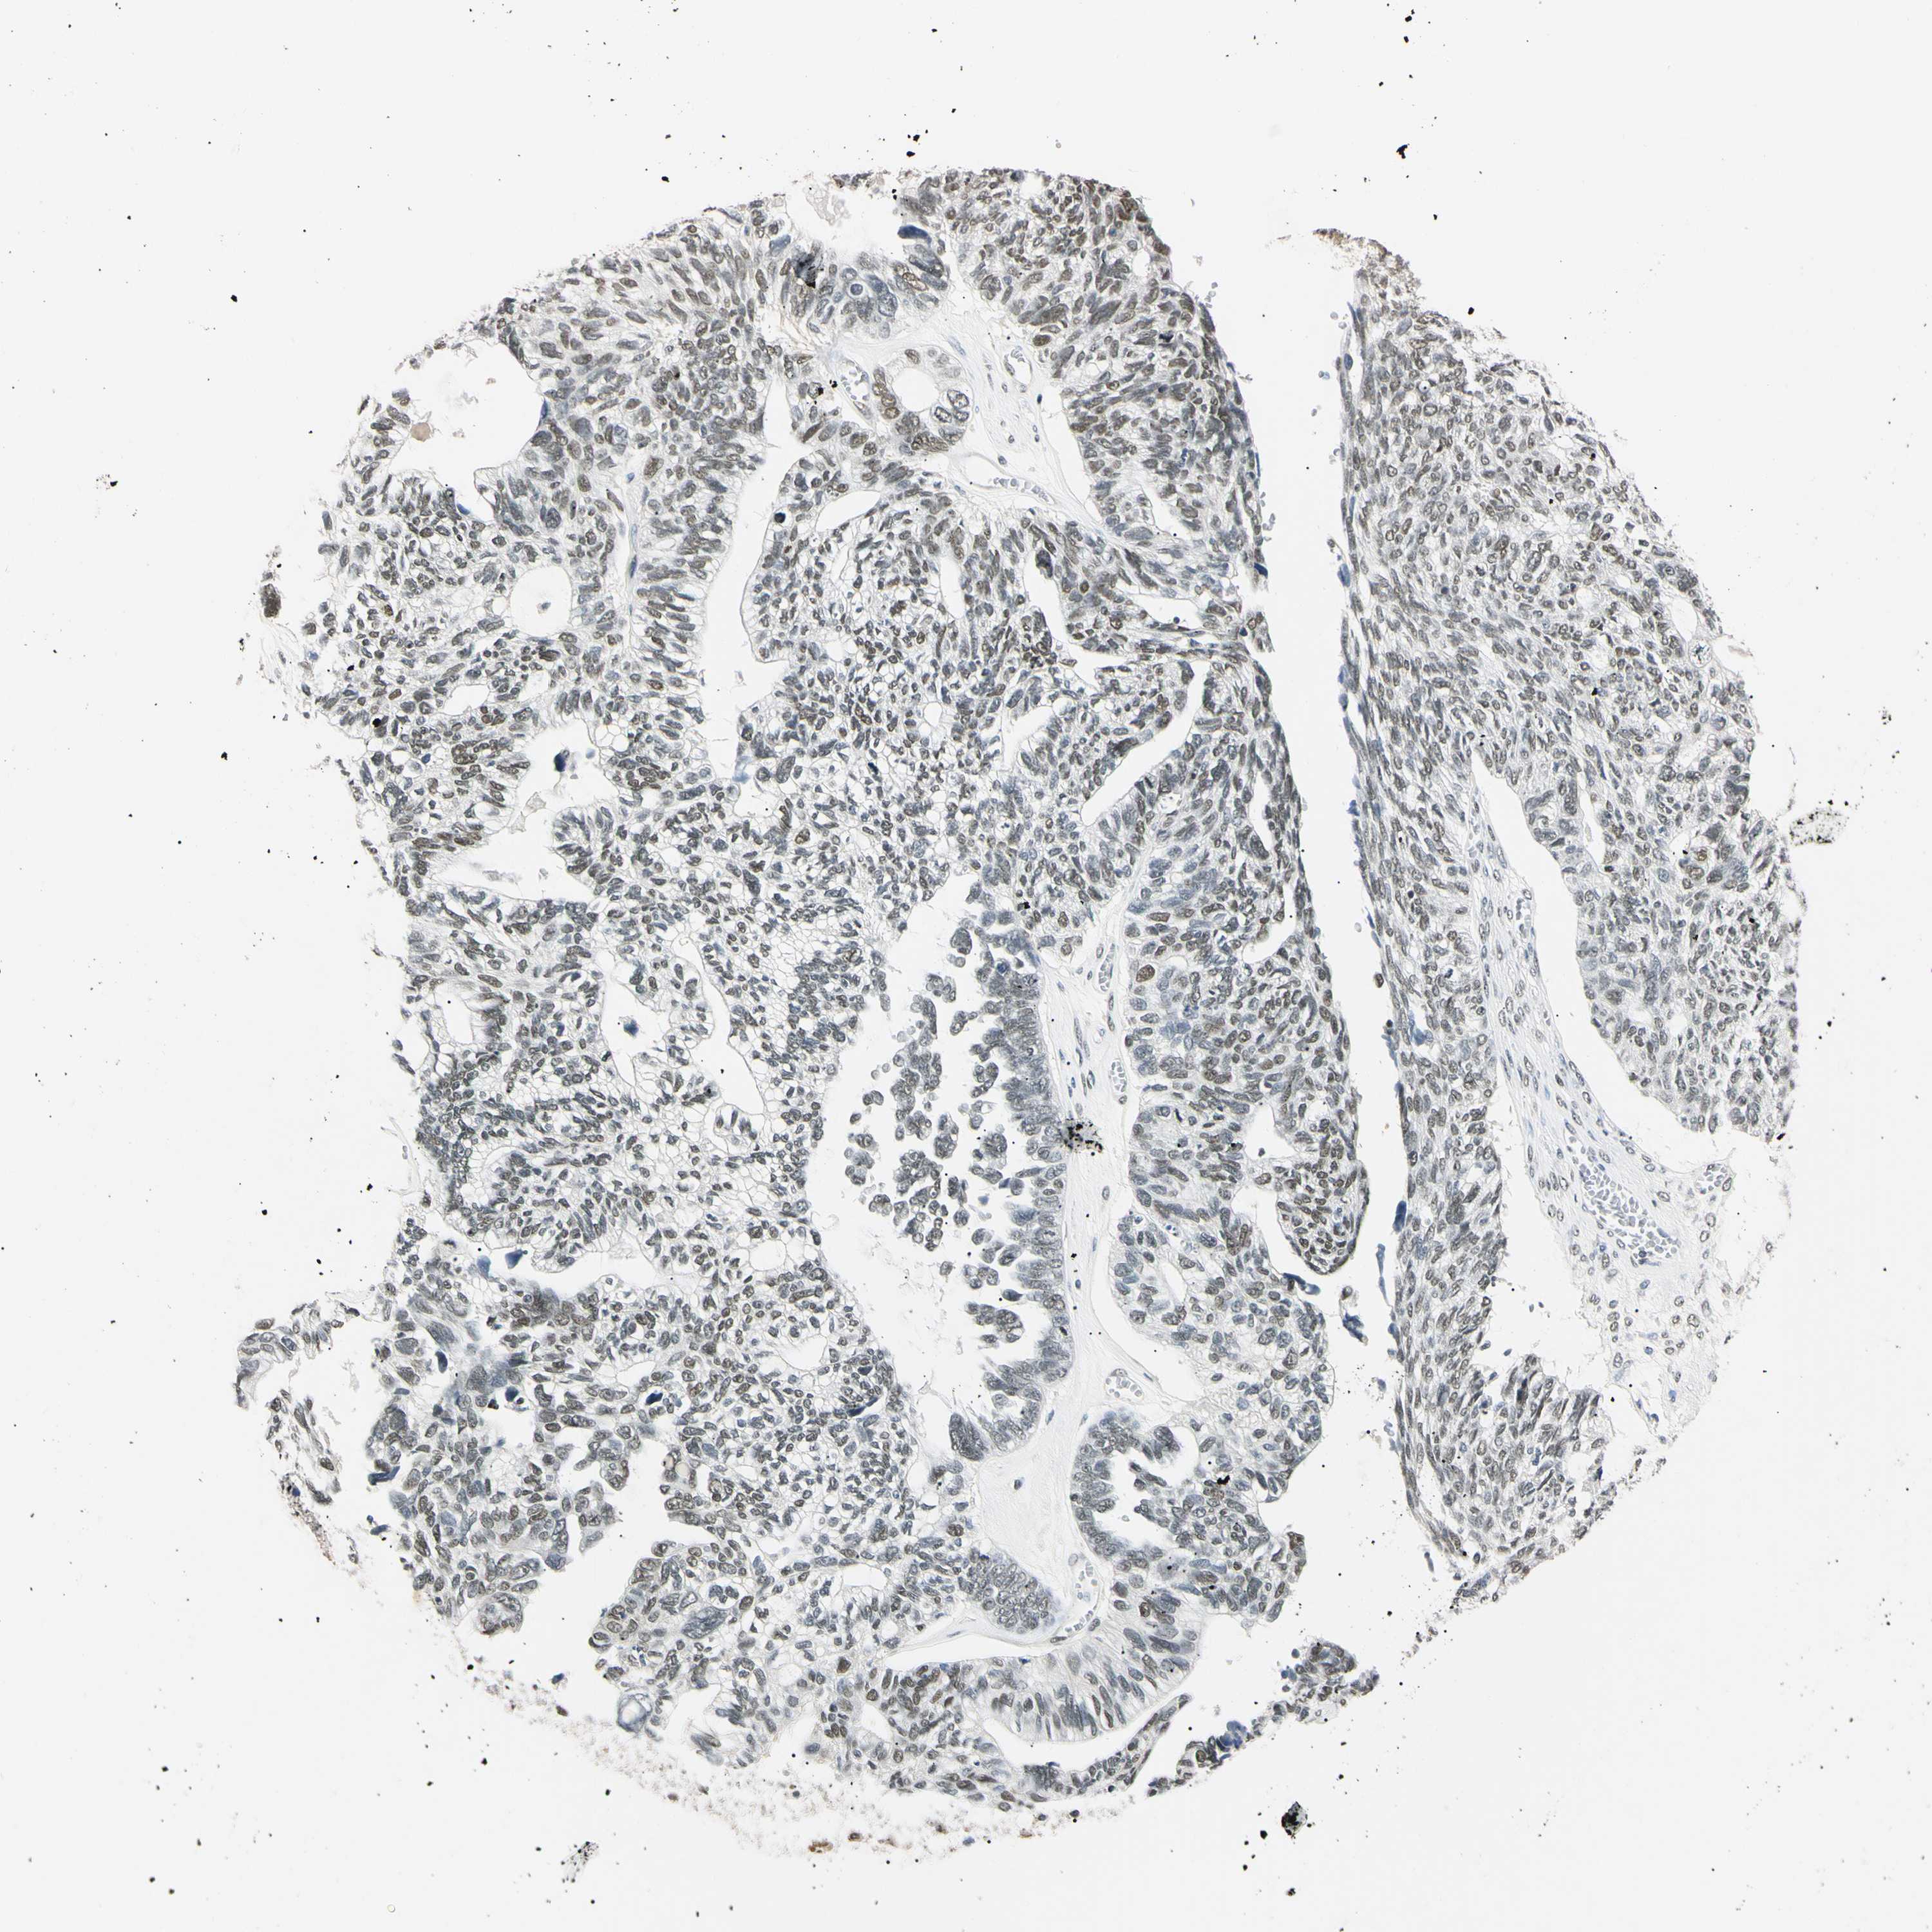

OVARIAN CANCER - Protein expressioni

A mouse-over function shows sample information and annotation data. Click on an image to view it in a full screen mode. Samples can be filtered based on level of antibody staining by selecting one or several of the following categories: high, medium, low and not detected. The assay and annotation is described here.

Note that samples used for immunohistochemistry by the Human Protein Atlas do not correspond to samples in the TCGA dataset.

Antibody stainingi

Antibody staining in the annotated cell types in the current human tissue is reported as not detected, low, medium, or high, based on conventional immunohistochemistry profiling in selected tissues. This score is based on the combination of the staining intensity and fraction of stained cells.

Each image is clickable and will lead to virtual microscopy that enables deeper exploration of all samples and also displays staining intensity scores, fraction scores and subcellular localization as well as patient and tissue information for each sample.

Antibody HPA008751

Antibody CAB005227

Cystadenocarcinoma, mucinous, NOS